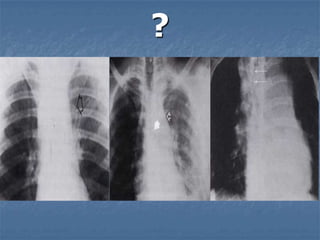

NEUMOTÓRAX TENSIÓN

Acumulación de aire en el espacio pleural, desde el

pulmón o por herida en la pared produciendo el

colapso del pulmón.

Dolor, falta de aire, dificultad respiratoria,

taquicardia, hipotensión, respiración paradójica

Desviación de la tráquea, ausencia de murmullo

vesicular, timpanismo, distensión de las

venas del cuello y cianosis.

¡¡¡PUNSION PLEURAL: 2o. EILMC Y SELLO DE AGUA!!!

?

NEUMOTÓRAX ABIERTO

Entrada de aire al espacio pleural por la

herida en la pared torácica con colapso

pulmonar.

Cubrir el defecto por 3 lados y dejar uno

abierto

Sello de agua distal al defecto

Tratamiento quirúrgico definitivo.

TÓRAX INESTABLE

Fractura de 2 o más costillas en dos o

más lugares con pérdida del soporte

óseo de un segmento del tórax.

Contusión pulmonar y dolor, respiración

superficial, respiración paradójica,

crepitación ósea, enfisema subcutáneo.

Radiografía de tórax.